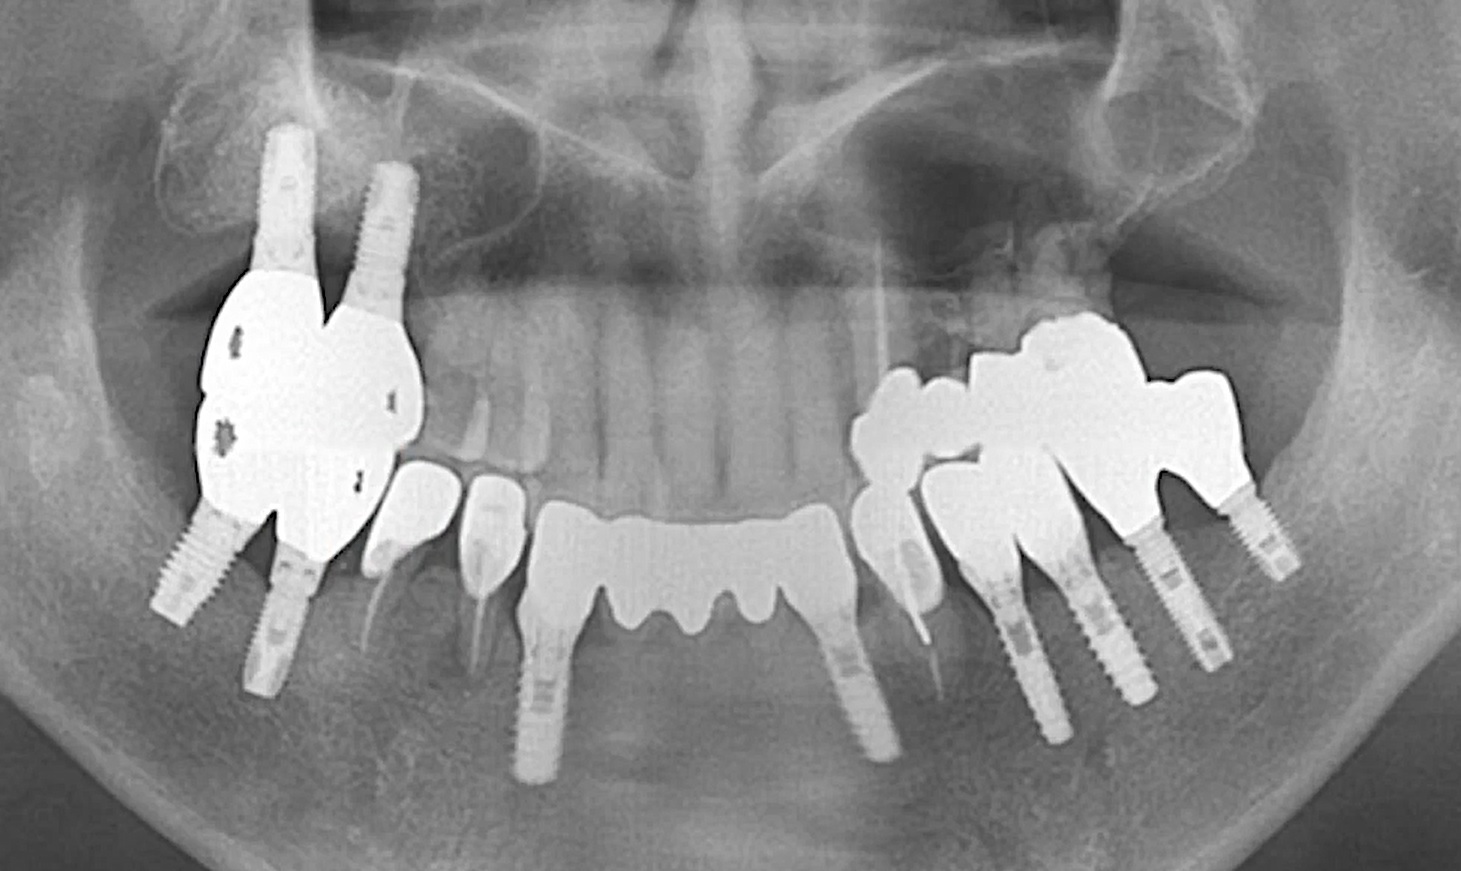

1 6 7 8